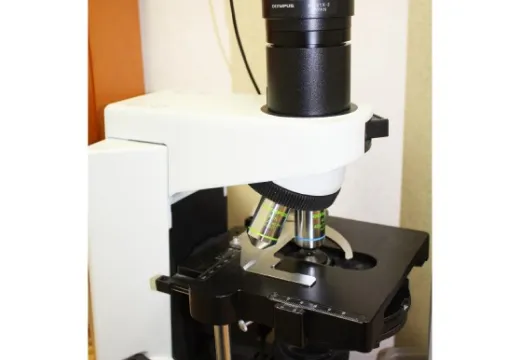

位相差顕微鏡

口の中の細菌をモニター画面に映します。